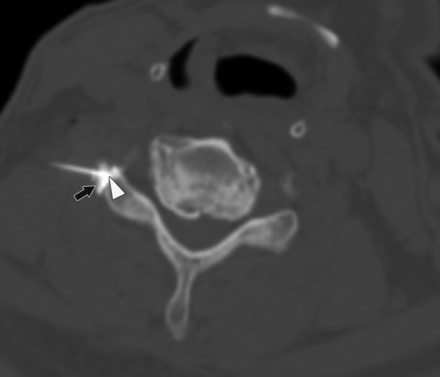

A 59-year-old man with right-neck pain radiating to the hand who had a CT-guided CTSI of the right C6 nerve root. The needle angle is 46°, and the tip of the needle is in the extraforaminal location (arrowhead) abutting the facet. The contrast is seen in the extraforaminal region (black arrow).